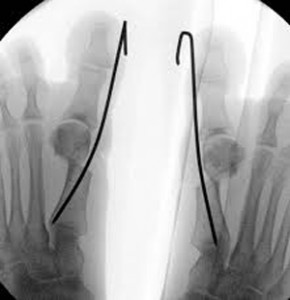

Η μέθοδος αυτή ονομάζεται διαδερμική – ελάχιστα παρεμβατική μικροχειρουργική του ποδός (MIS Minimaly invasive foot surgery), και διορθώνει ένα μεγάλο μέρος των παραμορφώσεων του άκρου ποδός.

Κατά τη διάρκεια της δεκαετίας του 1990 και 2000 ο Mariano de Prado και Pedro Luis Ripoli εξέλιξαν τις διαδερμικές οστεοτομίες με την χρήση υψηλής ενέργειας γλυφάνων (burrs) υπό ακτινοσκοπικό έλεγχο και βελτίωσαν μερικές παραμέτρους ( χρήση υλικών οστεοσύνθεσης ) των τεχνικών του Isham.

Χρησιμοποιώντας ειδικά μικροχειρουργικά εργαλεία, ειδικά υψηλής ενέργειας γλυφάνων (burrs) και ειδικό ακτινοσκοπικό μηχάνημα διορθώνονται οι παραμορφώσεις του ποδός.